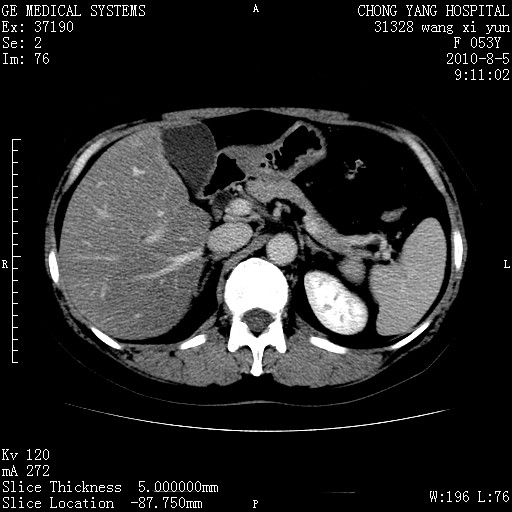

标题: CT28214:F41Y 血尿二十天,建议盆腔平扫加增强。

胆管细胞ca?

1)考虑肝左叶胆管细胞癌。2)脂肪肝。

支持胆管细胞ca。